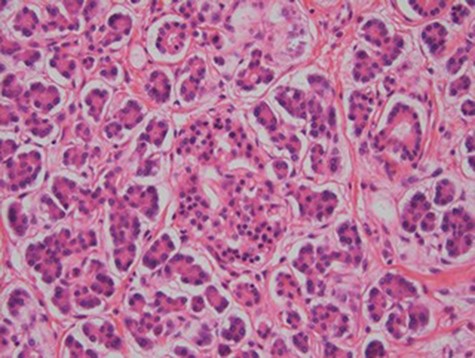

At laparoscopy, there were very dilated and inflamed loops of small bowel, and the appendix appeared normal macroscopically. Due to the extent of bowel dilatation obscuring adequate laparoscopic vision and assessment, decision was made to convert to an open procedure. At laparotomy, there was a nodular mass in the jejunal mesentery measuring about 3 cm in diameter with central necrotic tissue (Fig. 1). As it was adherent to the surrounding bowel, a limited small bowel resection was performed (Fig. 2) with side to side stapled anastomosis. Histology revealed normal small bowel wall with a mesenteric nodular mass comprised of architecturally normal pancreatic tissue including exocrine ducts and endocrine islets of Langerhans (Figs 3–5), consistent with a diagnosis of mesenteric heterotopic pancreas. His post-surgical recovery was uneventful and was discharged after five days of stay in hospital. He had an outpatient magnetic resonance imaging (MRI) of the pancreas which reviewed normal pancreas tissue, and he was followed up three months post-surgery.

Heterotopic pancreas was first described by Jean Schultz in 1729 and histologically confirmed by Klob in 1859 [1]. One proposed theory is that during the development and rotation of the foregut and fusion of the ventral and dorsal buds of pancreas, small islands of pancreatic tissue are separated and continue to develop in the ectopic locations [3]. Mesenteric heterotopic pancreas in paediatric patients has been rarely described in the literature [4]. Most lesions are solitary, ranging from 0.2 to 5 cm and commonly composed of all components of the normal pancreatic tissue [1]. Most cases of HP are found incidentally during upper abdominal surgery and imaging or at autopsy. However, depending on the location, size and involvement of the structure, patients can present with symptoms secondary to pancreatitis, bowel obstruction, bleeding, intussusception, perforation and malignancy [1,2]. In this case report, the 7-year-old boy presented with severe abdominal pain which mimicked appendicitis, and an inflammatory mass was found.

Our patient had type 1 heterotopic pancreas, which is the most common type.